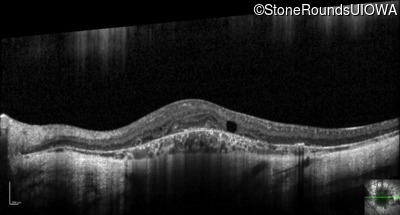

Optical Coherence Tomography - Right - 20/25 -2

Exemplar / OCT Stack

Optical Coherence Tomography - Left - 20/32